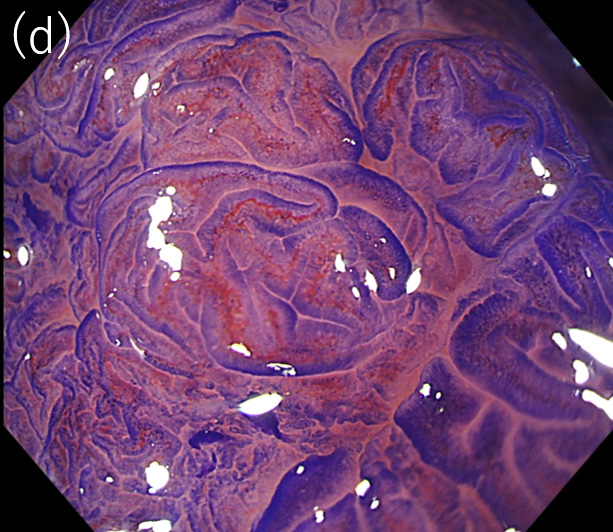

〈図3〉 XZ1200による30mm大Is+IIa(LST-G)病変

(病理診断:Adenocarcinoma, tub1, in tubular adenoma, pTis, Ly0, V0)に対する観察像

(d)クリスタルバイオレット染色後の拡大観察像(pit pattern:Ⅳ)